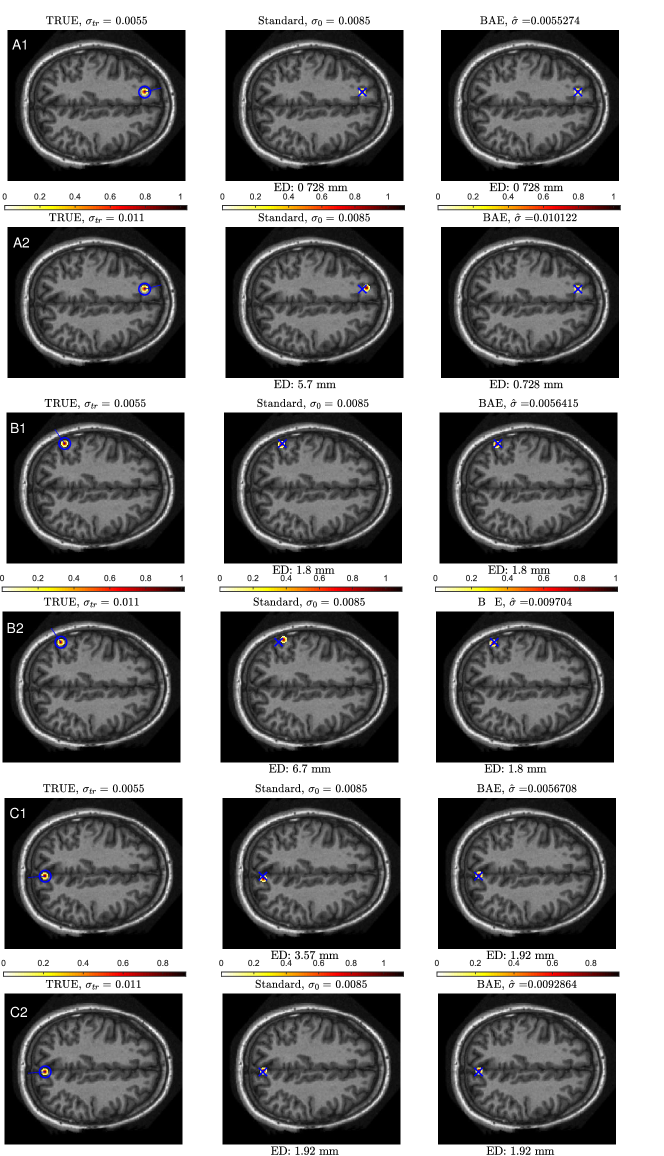

To demonstrate the simultaneous dipole and skull conductivity reconstruction, we used two test cases with different skull conductivities. The EEG data was computed using the accurate model that had either skull conductivity 0.0055 or 0.011 S/m, a single radial dipole source, and signal to noise ratio 30 dB. In Figure 2, we show first the test set-up, then the dipole-scan reconstruction with the standard lead field that has skull conductivity 0.0085 S/m, and finally the proposed Bayesian error modelling result. To ease comparisons, we calculated the Euclidean distance (ED) (in milli meters) between the actual and reconstructed source. It can be seen that the proposed uncertainty modelling improves the source reconstructions when compared to the solution of the standard model. Moreover, the estimates for the skull conductivity are close to the true skull conductivities.

Figure 2: Left column: Test cases with three different source locations and two different skull conductivity values, either lower (0.0055 S/m) or higher (0.011 S/m) than the standard skull conductivity (0.0085 S/m). The blue circle and the line represent the true location and direction of the dipole source, respectively. Middle column: Source reconstruction results when the standard skull conductivity was used in the lead field. The ED values give the Euclidean distance between the true and reconstructed source. The true location is denoted with a blue cross. Right column: Simultaneous skull conductivity and source location reconstructions with the proposed Bayesian uncertainty modelling approch. As can be seen, the proposed approach improves the source localization compared to the results with the standard model and additionally achieves to estimate the skull conductivity.